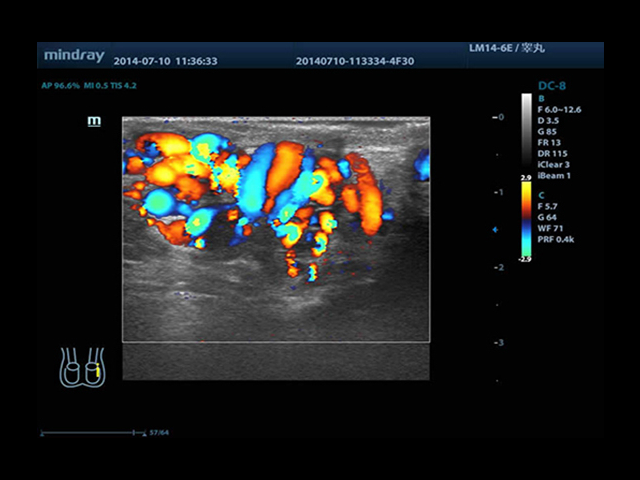

Mindray DC-8 Exp оснащен новым поколением датчиков с увеличенным количеством элементов и инновационной технологией "3T". Это позволяет достичь высокой детализации и качества изображения. Благодаря новейшей технологии iFlow, можно визуализировать даже самые мелкие сосуды и кровеносные пути.

Сверхширокополосная нелинейная обработка изображений снижает визуальные шумы на 30% по сравнению с другими системами. Технология iClear позволяет устранить зернистость изображения, а iBeam (технология пространственного компаундинга) обеспечивает высокое качество сканирования органов и тканей под различными углами.

• HR-flow™ - режим отображения кровотока с высоким временным и пространственным разрешением для точной и однородной визуализации сосудов, в том числе самых мелких